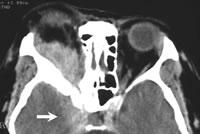

眼部CT檢測圖(1)①眼球內病變:白瞳症、視網膜母細胞瘤、脈絡膜骨瘤、黑色素瘤及轉移瘤等。②眼眶病:有眼球突出或疑有眶內腫瘤,眶內炎症及寄生蟲,視神經及眼外肌病變,血管性病變如靜脈曲張、動靜脈瘺、眶壁腫瘤及缺失畸型等。③眼外傷:異物、眼球破裂、骨折、軟組織血腫等。④眶鄰近結構病變。⑤視路病變等。(2)①水平層面;眼眶豎徑35~40mm,取3mm厚度需14個斷層面,可分別觀察眶下部、中部和上部大部分結構及形態。②冠狀層面:可顯示眶頂、眶底和眼外肌的厚度,甚至眼動靜脈等小結構,彌補水平CT的不足。③矢狀層面,在平行於眶軸的層面上,可顯示眶上、下壁,上、下直肌及眶內神經的全程。